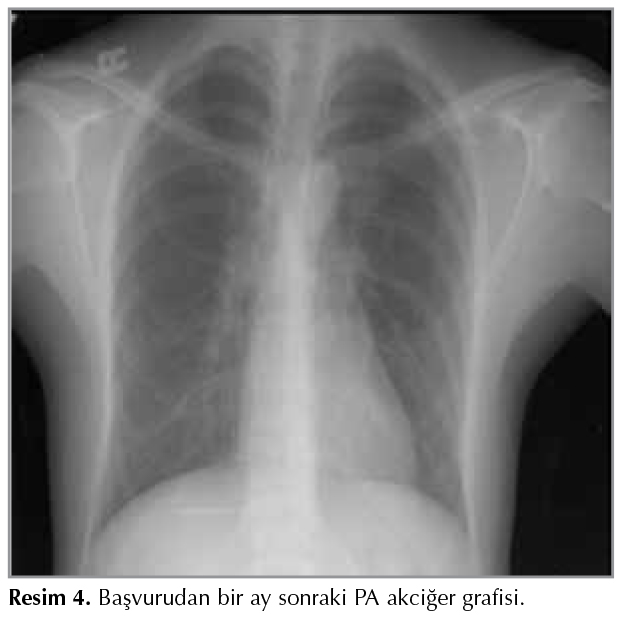

Laboratuvar tetkiklerinde; l?kosit: 4800 x 103 /L, eozinofil %0.4, Hb: 12.8 g/dL, sedimentasyon: 55 mm/saat, CRP: 6.7 mg/dL, ALT: 18 U/L, ALT: 32 U/L, Anti-HIV:? negatif, balgam ARB incelemesi negatif geldi. Yapılan t?berk?lin deri testi (TDT) negatif saptandı. Sistemik lenf nodu yapan nedenleri araştırmak amacı ile ?ekilen batın ultrasonografi (USG) normaldi, kollajen doku markerları (ANA, ANCA, anti-ds DNA), Brucella Rose Bengal testi, CMV-Rubella-Toxoplasma PCR negatifti.? HSV-1 IgM sınırda pozitif, HSV-1 IgG pozitif, EBV VCA IgG ++, EBV IgM negatif saptandı.? Viral solunum yolu panelinde ise C. pneumoniae IgM zayıf pozitif olup diğer parametreler negatif idi. Tiroid fonksiyon testleri normaldi. Hasta boyunda mobil lenf nodu saptanması nedeni ile tanısal ama?lı ?rnekleme i?in ?ncelikle kulak burun boğaz kliniğine y?nlendirildi. Sağ juguler yerleşimli 1 cm'lik lenf nodu eksizyonel biyopsi patoloji sonucu histiyositik nekrotizan lenfadenit; KFH ile uyumlu olarak raporlandı (Resim 3). Nonspesifik tedaviden 20 g?n sonra klinik olarak d?zelen, palpabl lenf nodları regrese olan hastanın kontrol PA akciğer ve toraks BT'sinde sağ hiler lenf nodunda progresyon saptanmadı (Resim 4,5). Genel durumu stabil olan hastaya ?? ay sonrasına kontrol ?nerildi.

Resim 4